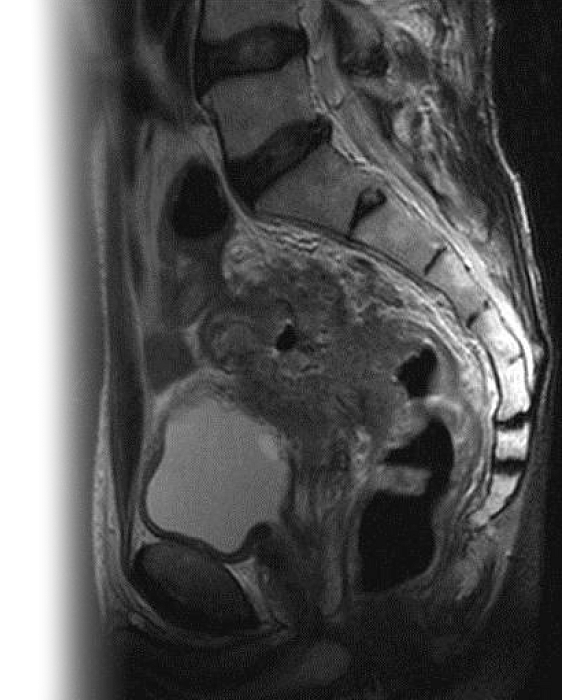

МРТ органов малого таза и наружных половых органов у мужчин – важный метод исследования, который позволяет визуализировать предстательную железу, мочевой пузырь, семенные пузырьки, прямую кишку, наружные половые органы.

Как проводится МРТ органов малого таза и наружных половых органов у мужчин?

Перед укладкой в томограф необходимо снять все металлические предметы. После этого пациент ложится на стол сканера, который постепенно перемещается в аппарат. Во время сканирования следует лежать неподвижно, чтобы получаемые изображения были четкими и неискаженными.